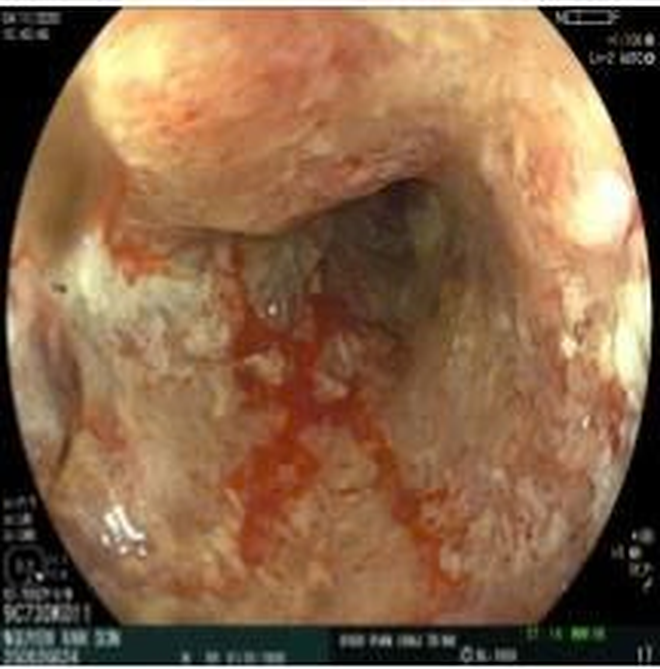

Tuy nhiên, dựa trên bệnh sử kéo dài và yếu tố nguy cơ tuổi cao, bác sĩ chỉ định nội soi đại–trực tràng bằng hệ thống nội soi mới nhất của Fujifilm tích hợp trí tuệ nhân tạo (AI). Hình ảnh nội soi cho thấy tổn thương u sùi chiếm toàn bộ chu vi trực tràng, cách rìa hậu môn 15 cm, dễ chảy máu.

Công nghệ AI tích hợp trên hệ thống nội soi hỗ trợ phân tích hình ảnh theo thời gian thực, khoanh vùng nghi ngờ ác tính và giúp bác sĩ đánh giá bề mặt tổn thương rõ ràng hơn. Việc ứng dụng AI giúp giảm nguy cơ bỏ sót các tổn thương dù là nhỏ nhất và tăng độ chính xác trong chẩn đoán ngay từ thủ thuật đầu tiên